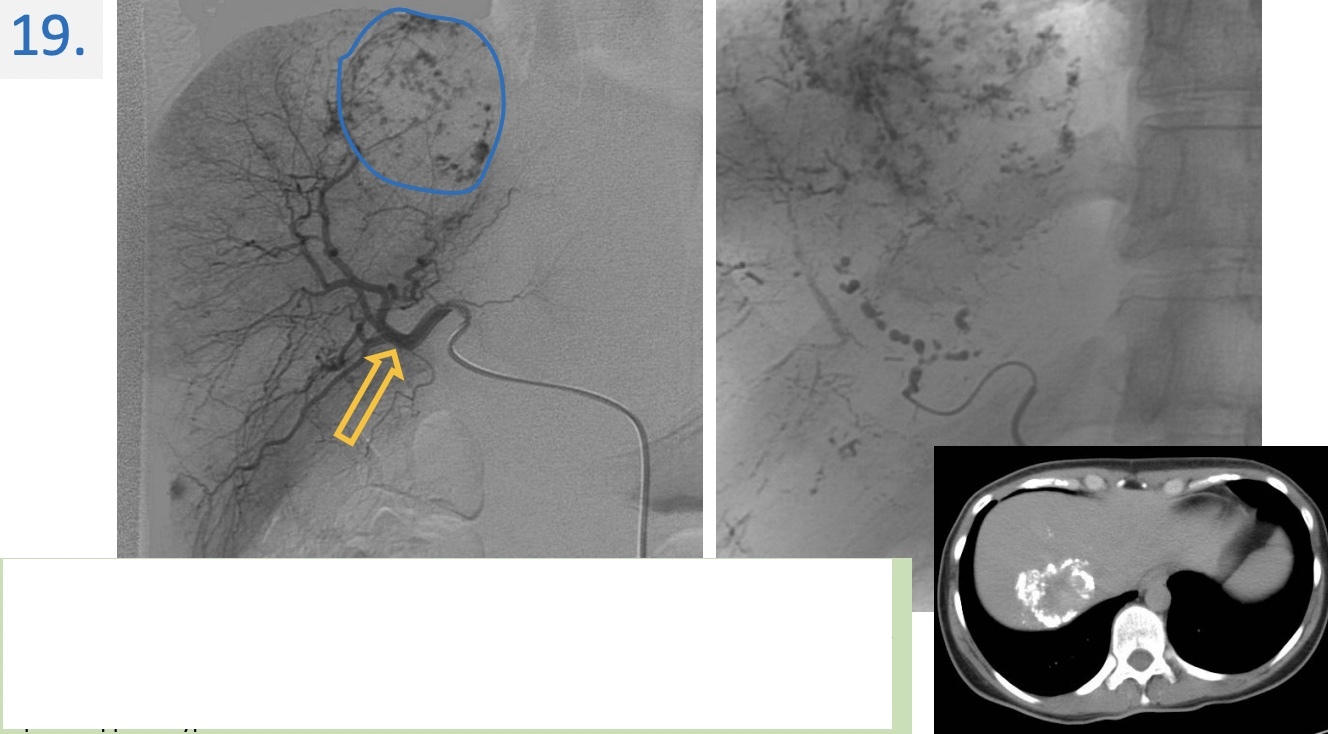

19

Region:

liver right subcostal view

Diagnosis:

Hepatic hemangioma